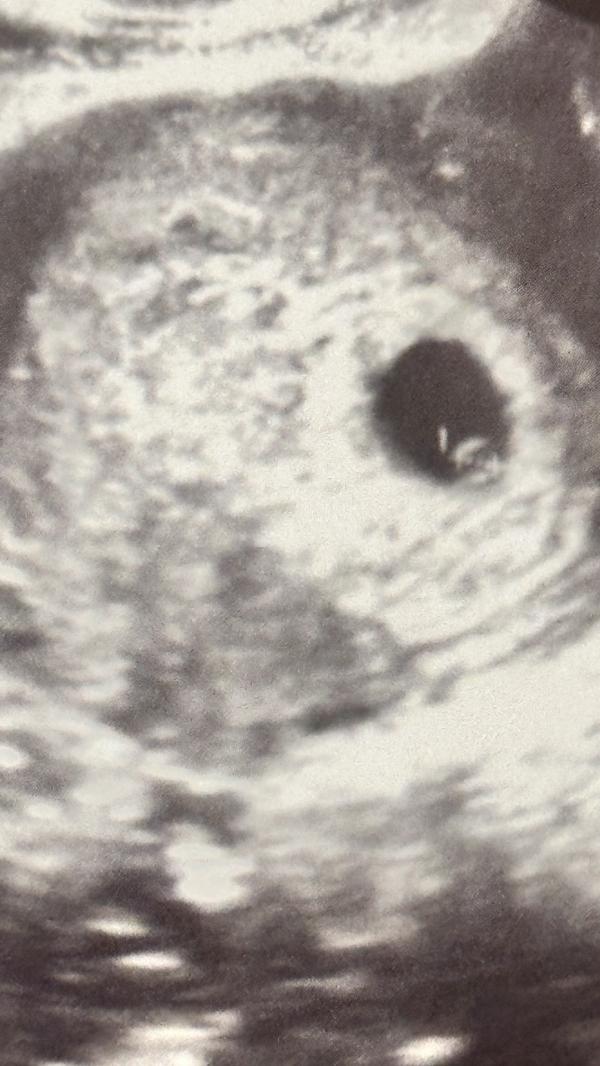

Узи показало, что малыша пока не видно: что делать и когда ждать результатов следующего обследования?

Были сегодня на узи, нашего малыша пока еще не видно 🥹